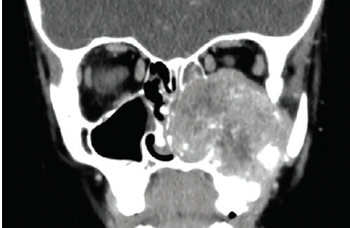

A 9-year-old boy with no significant medical history presented to the emergency department with 2 days of painless blurry vision. What's the diagnosis?